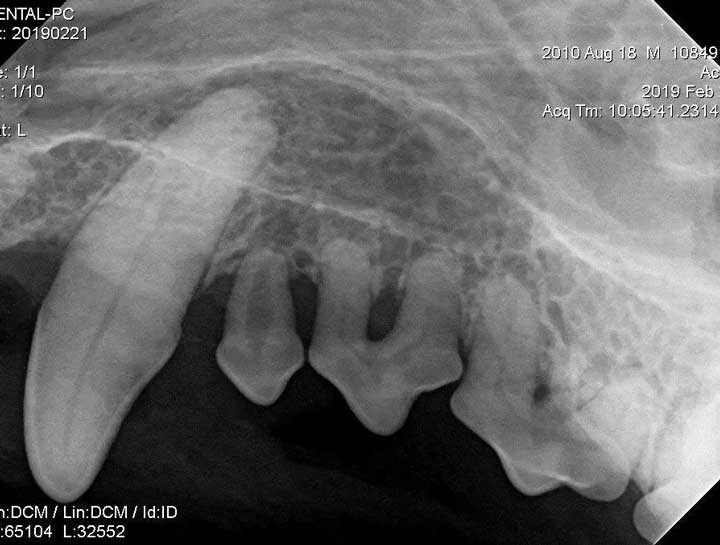

Digital Dental Radiology

Insight into underlying issues.